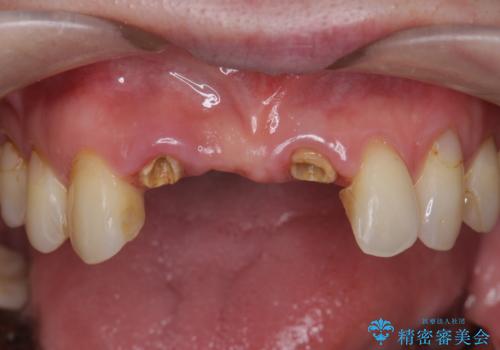

美容外科による不自然なかぶせもので、前歯がコンプレックスに。自然なセラミックにやりかえ 30代女性